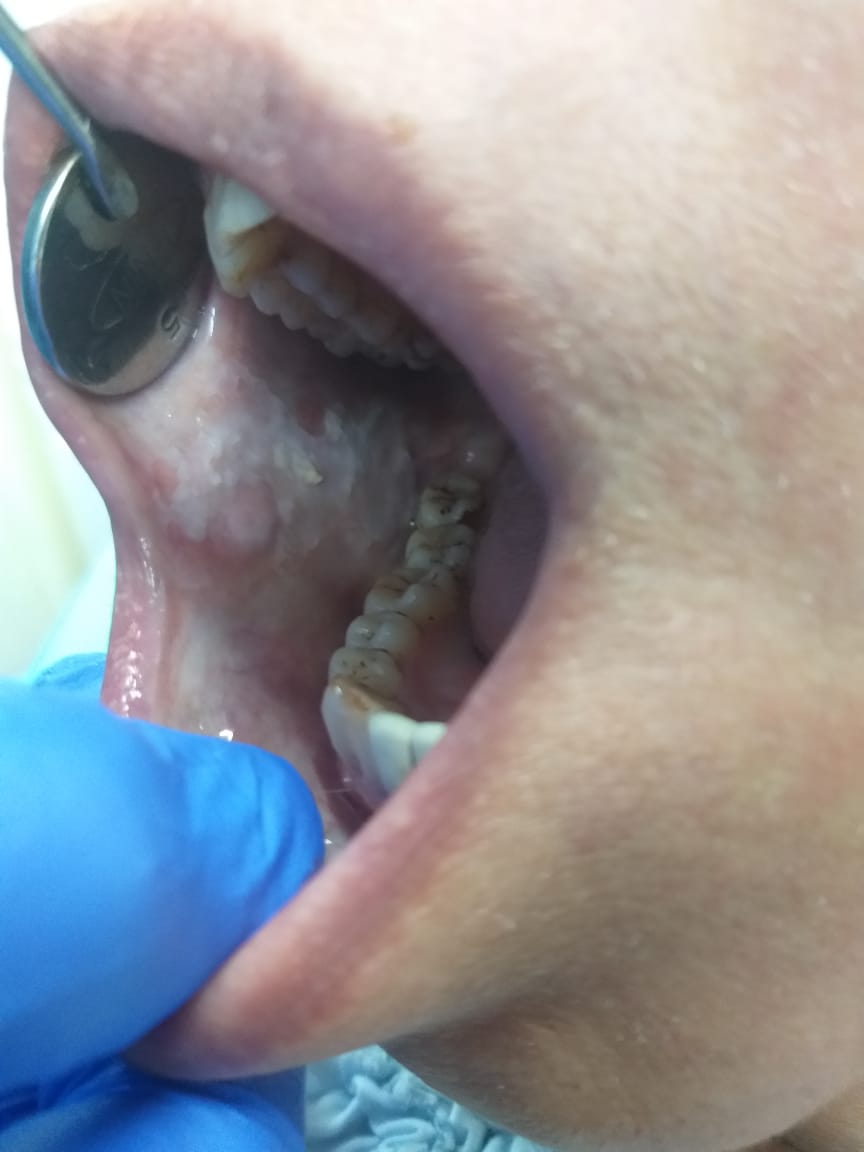

Tongue disorders, such as geographic tongue and black hairy tongue, present unique challenges in oral health management. Geographic tongue, characterized by map-like patterns on the tongue’s surface, can cause discomfort and sensitivity. Black hairy tongue, marked by a dark, furry appearance due to the buildup of dead cells and bacteria, often results from poor oral hygiene or certain medications. Both conditions typically respond well to improved oral hygiene practices and, if necessary, specific treatments to manage symptoms and prevent recurrence.